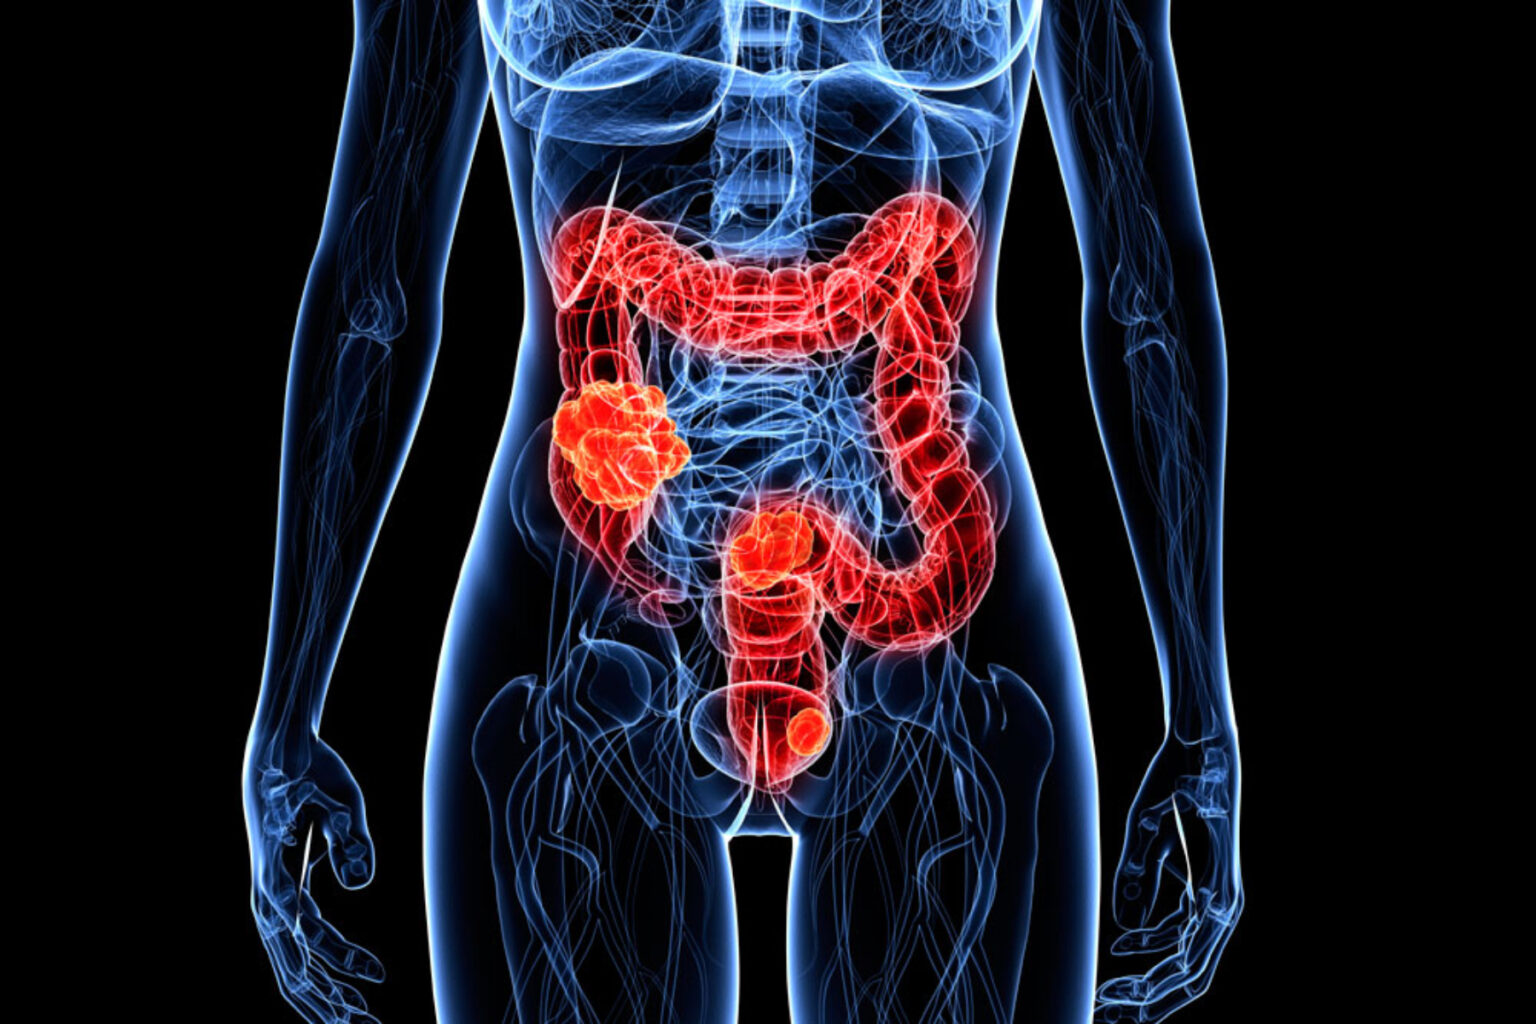

Μια νέα έρευνα, διαπίστωσε πως οι πάσχοντες με καρκίνο παχέος εντέρου που έχουν και σακχαρώδη διαβήτη, έχουν αυξημένες πιθανότητες να πεθάνουν πρόωρα λόγω των επιπλοκών του διαβήτη.

Η ανάλυση αφορούσε 59.202 ενήλικες με καρκίνο παχέος εντέρου, που υποβλήθηκαν σε εγχείρηση για την αφαίρεση όγκου.

Από αυτούς, οι 9.448 εμφάνισαν υποτροπή του καρκίνου και 21.031 πέθαναν από διάφορες αιτίες κατά την περίοδο μελέτης.